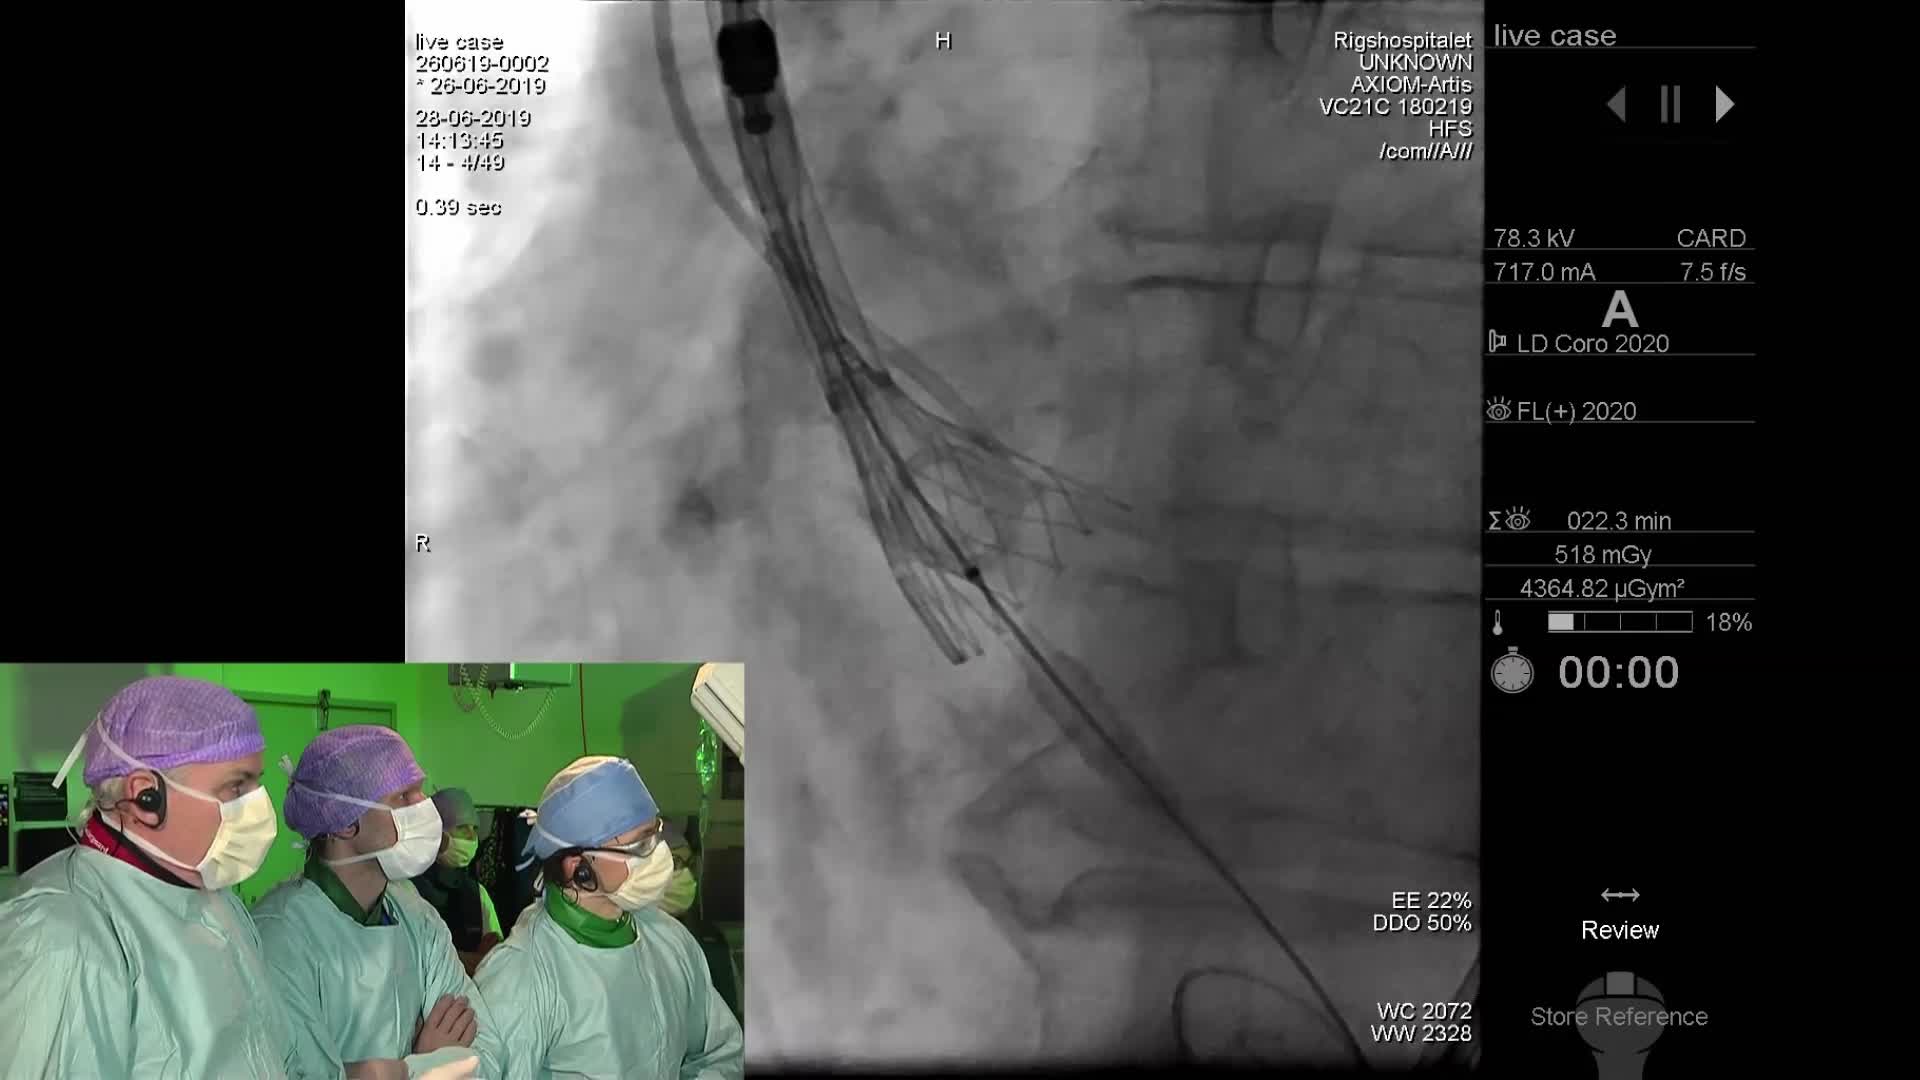

Cathlab Live Cases